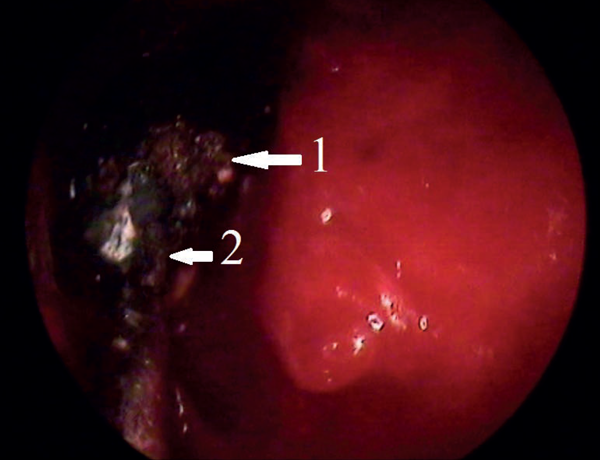

Figure 3: Endoscopic view: 1 - frontal osteoma; 2 - diode laser.

She was informed beforehand that in case of failure of the endoscopic surgery the tumour would be removed by an open coronal approach. In January 2013 the osteoma was removed under general anaesthesia and controlled hypotension with endoscopic control using a 3D electromagnetic navigation system via endonasal approach. After the tumour was mobilised into the sinus cavity (Figure 2), reduction of its size was necessary to release it from the sinus. Mobilised osteoma was reduced by diode laser applied in contact mode (power 10 W) (Figure 3) and then removed through the nasal cavity (Figure 4). Vaporisation of mobilised bone tumour was held around its circumference with exposure time of 8-10 seconds. When it reached a sufficient size for removing through the expanded frontonasal ostiae, it was extracted by an aspirator. Histological examination showed a mixed osteoma, containing dense and mature bones, fibrous tissue and collagen fibres (Figure 5). A right eyelid oedema was in the early postoperative period. This situation was not accompanied by damage of the optic nerve and violations of the mobility of the eyeball. Systemic antibiotic therapy, glucocorticoids and diuretics were initiated immediately and eyelid oedema passed off within two days. The control CT scan on the third day after surgery showed complete removal of tumours (Figure 6). The patient was transferred to out-patient treatment on the seventh day after surgery. We recommended the use of topical steroids and ENT and ophthalmology dynamic observation.